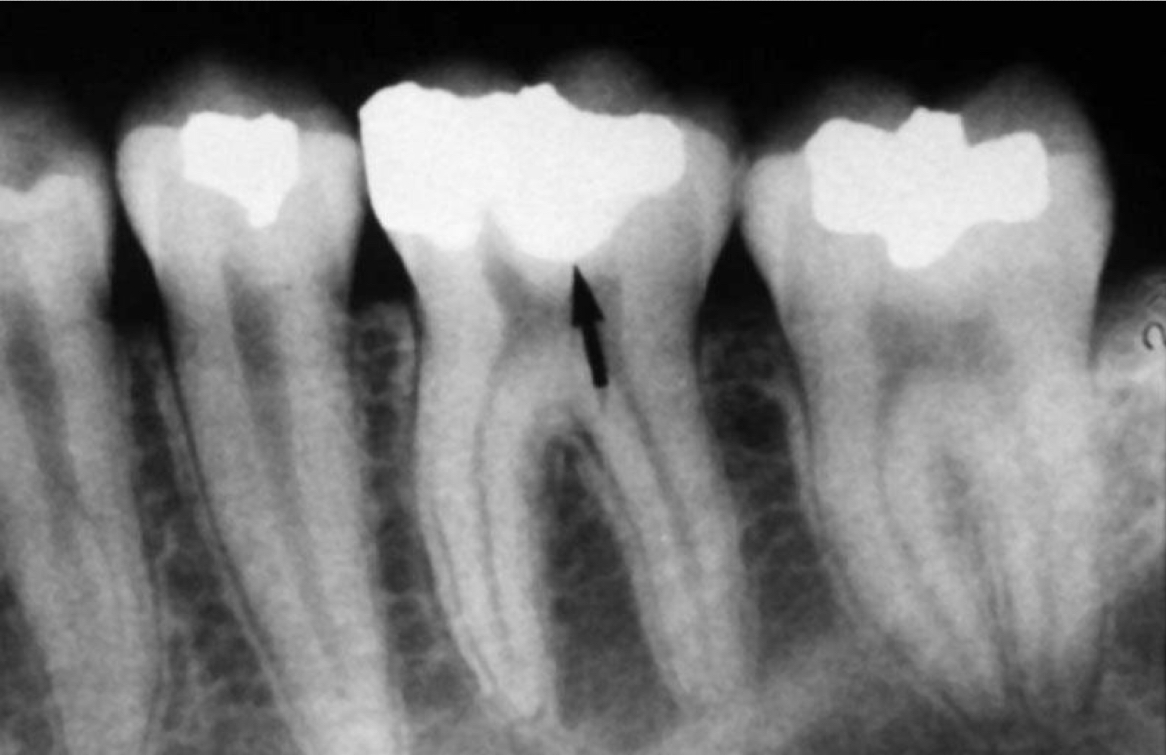

Gutta percha

Silver points